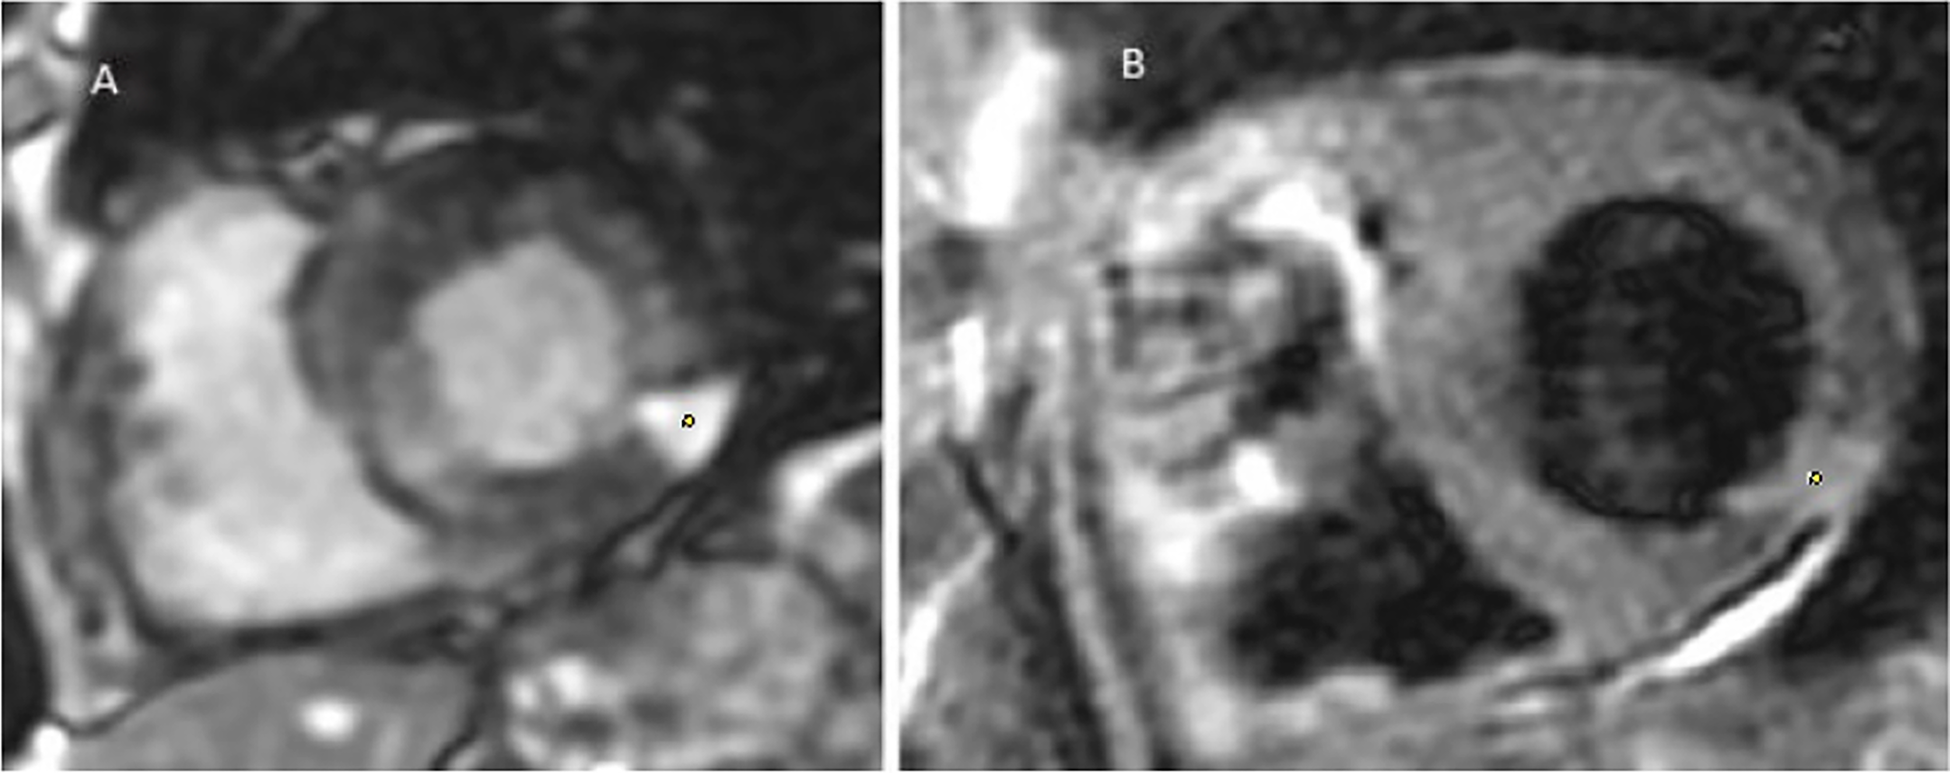

Figure 5

Multiparametric cardiac MRI from patient no. 1. Yellow spots showing late gadolinium enhancement at the apex as well as an anterior and lateral sub endocardiac and midwall enhancement.

In response to the imaging findings, the patient was given a second and third 10 ml dose of Bothrofav® at the 12-h and 15-h marks, respectively. After reporting a subjective sensation of a headache without any neurological deficit 22 h post-bite, a cerebral MRI was performed (Figure 7). The MRI detected multiple strokes, especially involving the PICA and junctional territories. Furthermore, due to the alarming rise in troponin to 18,451 pg/ml by the 19th hour, a cardiac MRI was carried out on Day 3. This MRI revealed a T2 hypersignal and late transmural lateral basal enhancement, indicative of a recent microvascular event. Multiple areas displayed late mediomyocardial or cocardial enhancement with fibrotic signs, suggesting cardiac amyloidosis (identified coincidentally) or myocarditis (Figure 8). However, unlike in the Patient No.1 case, the ECG did not exhibit any disruptions from the myocardial damage. After six days of hospitalization, the patient was discharged without any clinical aftereffects. He regained his physical activity level, matching his pre-envenomation state.

Figure 7

Patient no. 2 cardiac MRI: yellow spots showing Hypersignal latero basal and apico septal in T2 weighting, several patches of enhancement without coronary systematization frank: transmural latero basal and quasi transmural latero to the apex, as well as medio myocardial septal.